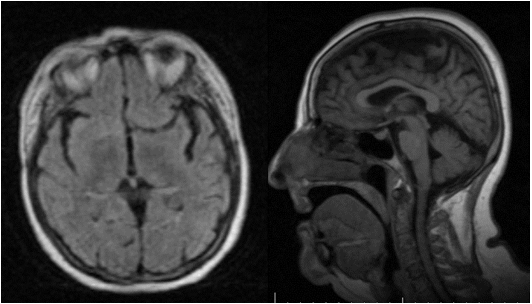

Figure 3 MRI of the brain without lesions FLAIR axial, sagittal, sagital.

Figure 4 T 2 brain MRI.

MRI has limited specificity for diagnosis, as well as for prognosis even though other neurological pathologies can be excluded. The axial and sagittal Flair images can be visualized in the MRI, as well as in the T2 images, there is no evidence of lesions in the cerebral parenchyma.